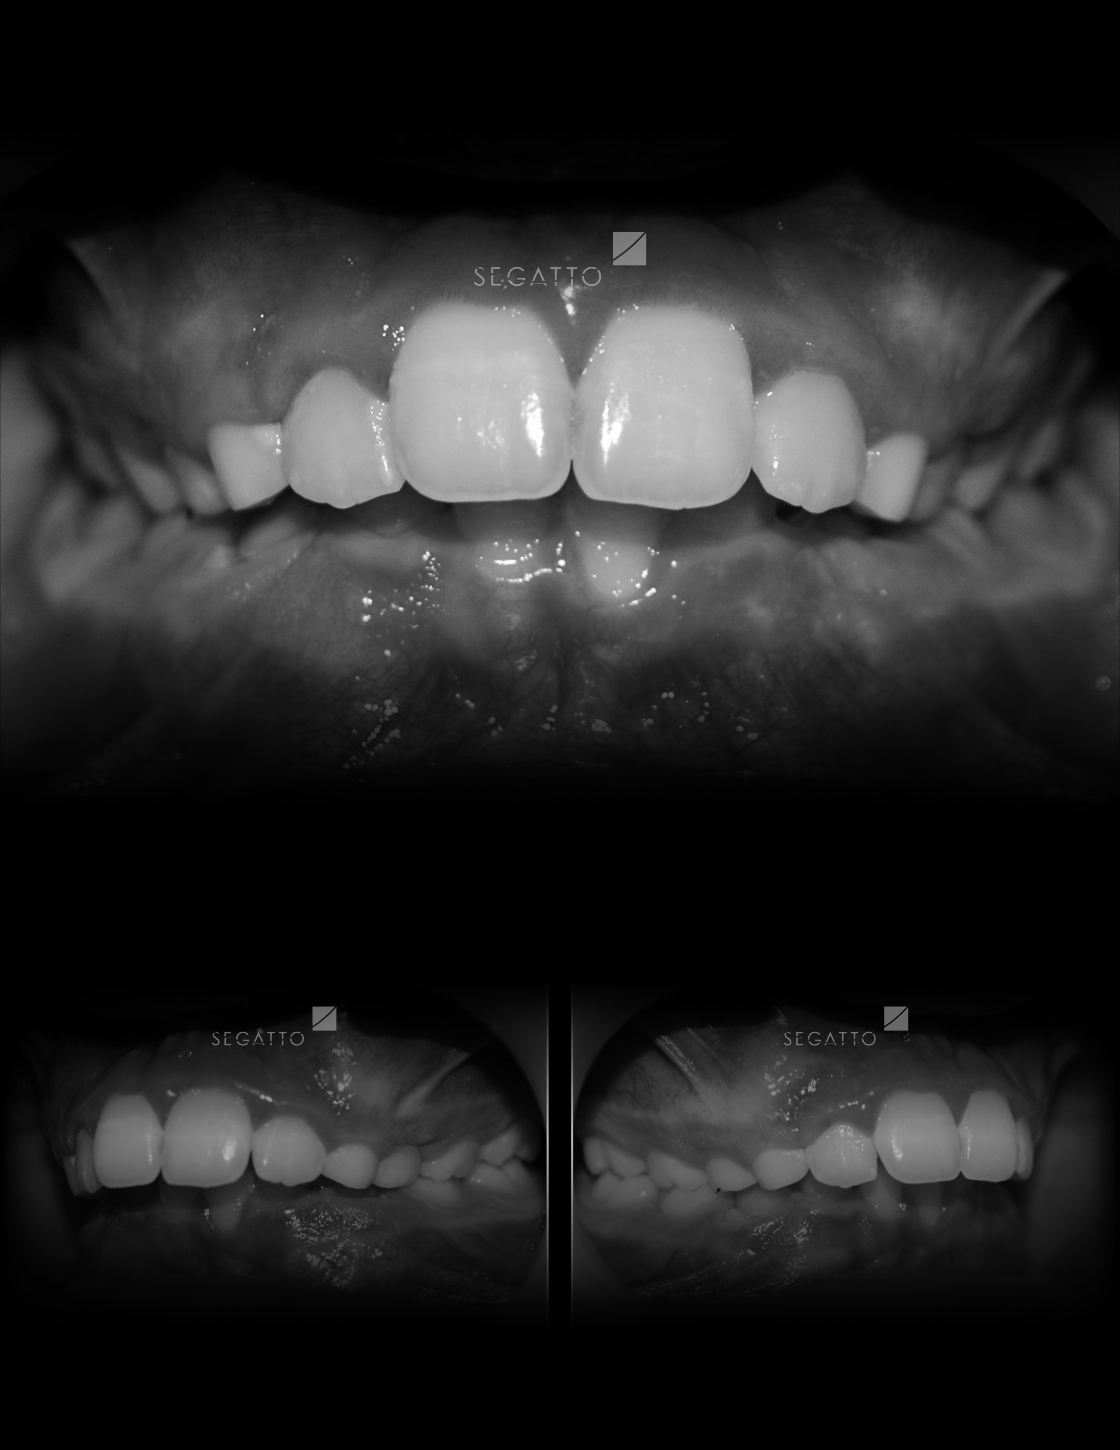

Orthodontics

Cases